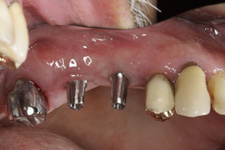

Bezzubá čelist je hlavní indikací pro ošetření pomocí implantátů. Zejména celkové zubní náhrady v dolní čelisti mají velice nízkou stabilitu a držení díky velkému úbytku kosti.

S pomocí zubních implantátů můžeme díky různým kotevním systémům (třmeny, kulové hlavy, Locatory) zajistit stabilitu a držení protézy nebo při použití většího počtu implantátů zhotovit pevné náhrady – můstky nalepené nebo našroubované na pevno na implantáty.

S těmito typy náhrad můžeme dosáhnout perfektní funkci, výbornou estetiku, fonetiku a současně zajistit u pacienta možnost dobré hygienickou péče a čištění, která je pro životnost implantátů velice důležitá.